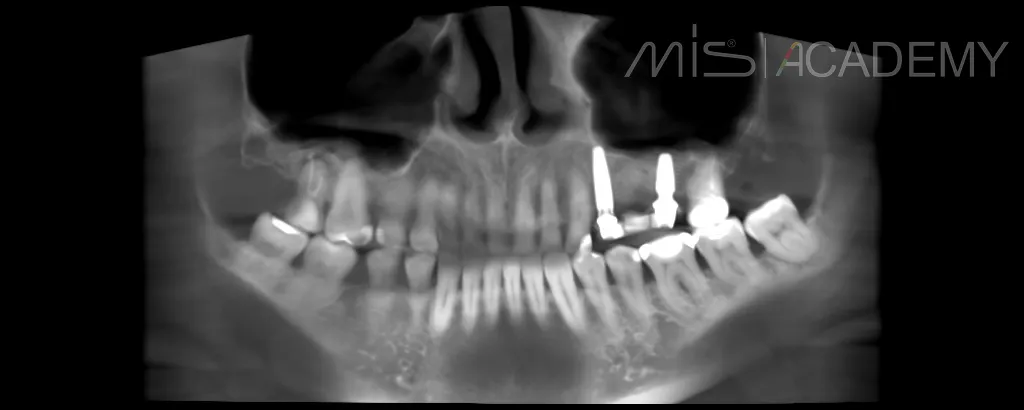

Произведено удаление зуба 2.4

— Одномоментная установка имплантата в области 2.4.

— Установка имплантата в области 2.6 с закрытым синус-лифтингом.

— Установка произведена с помощью хирургического шаблона.

— Импланты MIS C1 3.75×13 и 4.2х8.